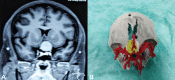

Three-dimensional (3D) printing technology in neurosurgery has gained popularity nowadays. Skull base contains many major neurovascular structures in a confined space, along with anatomical variations making surgical approaches to this region challenging. 3D-printed model of skull base tumors consists of the patient's bony skull base, actual tumor dimensions, and surrounding major neurovascular structures. We included a total number of five patients with skull base tumors (one case of planum sphenoidale meningioma, two cases of sellar tumor with suprasellar extension, and two cases of cerebellopontine angle tumor) and 3D-printed tumor model of each of them. These models were used for preoperative simulation and served as very true to life training tool. These help in increasing the efficacy of the surgeon, improves surgical safety and ergonomics. They were also used for patient counselling, educating about the disease, the surgical procedure, and associated risks.